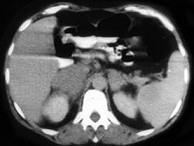

问题 男,65岁,腋下触及肿大包块,全身浅表淋巴结肿大,请结合所提供图像,选择最佳答案()

选项 A.双侧肾上腺腺瘤 B.双侧肾上腺增生 C.双侧肾上腺淋巴瘤 D.双侧肾上腺转移瘤 E.肾上腺癌

答案 C